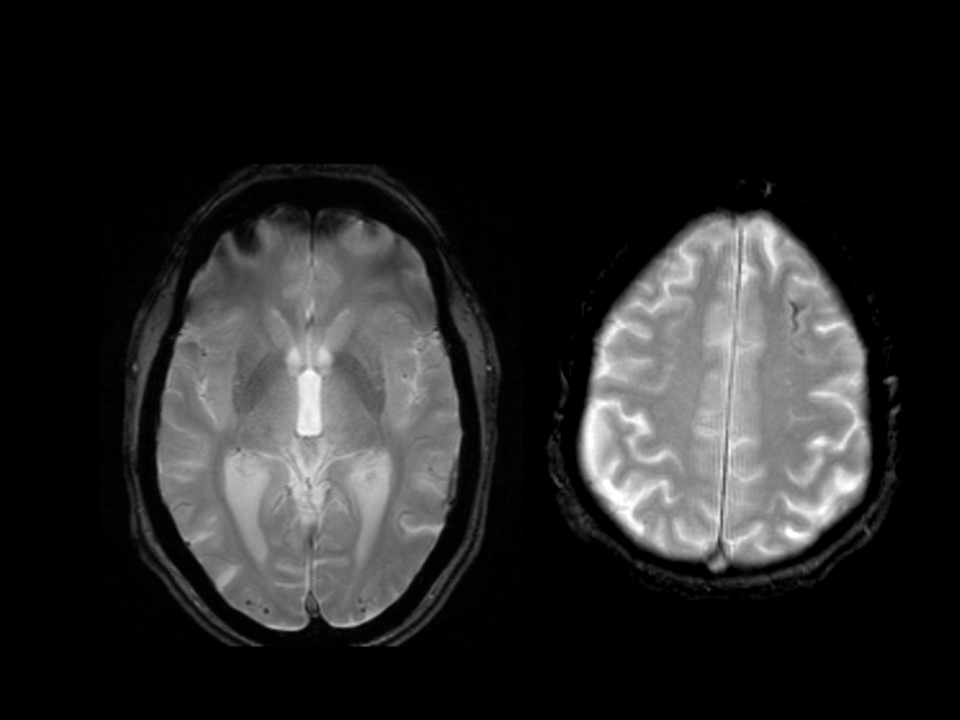

ARIA-E is caused by increased extravasation of protein-rich fluid resulting in vasogenic edema and/or effusion. MRI changes are best detected as bright signal on T2-fluid-attenuated-inversion recovery (T2-FLAIR) sequences.

ARIA-H is characterized by small deposits of blood containing hemosiderin, which can either be parenchymal (microhemorrhages) or superficial siderosis in the pial or subarachnoid space. These changes can be detected as dark signal on susceptibility-sensitive sequences, such as T2* gradient echo (GRE) or susceptibility-weighted imaging (SWI).

The core sequences for ARIA detection are T2-FLAIR and GRE. 3T scanners are recommended, as they detect abnormalities with higher sensitivity, although 1.5T scanners are also acceptable. It is of note that classification of ARIA-H is based on 2D GRE data, as these sequences have primarily been used in ARIA clinical trials. Efforts should be made to follow each patient with the same acquisition protocol, scanner, and coil. Detailed acquisition protocols for each MRI vendor can be found here.

An important differential for ARIA‑E is ischemic stroke. Both can present with non‑specific symptoms such as confusion, headache, and visual or gait disturbances. ARIA‑E edema appears as bright parenchymal hyperintensities on T2‑FLAIR, which can mimic ischemic stroke, but DWI can help distinguish the two—acute ischemic stroke shows diffusion restriction, whereas ARIA‑E does not.